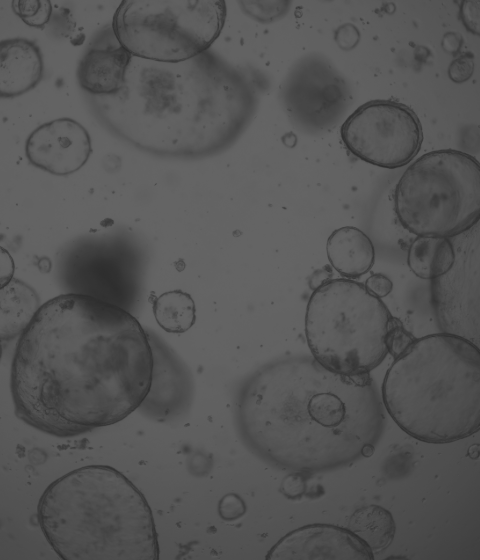

廈門模基生物科技有限公司致力于3D細(xì)胞培養(yǎng)核心原材料的研發(fā)與產(chǎn)業(yè)化升級,是國內(nèi)一家從科研做起,從實(shí)驗(yàn)研究中一路走來的全流程自主研發(fā)、自主生產(chǎn)的企業(yè)。目前公司的產(chǎn)品有基質(zhì)膠、類器官培養(yǎng)基、細(xì)胞因子、3D細(xì)胞培養(yǎng)耗材、3D細(xì)胞培養(yǎng)智能顯微鏡等。公司擁有4大技術(shù)研發(fā)中心:分子克隆和細(xì)胞編輯中心、實(shí)驗(yàn)動物中心、蛋白表達(dá)和純化平臺、類器官質(zhì)檢系統(tǒng)和自動化。